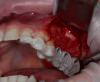

CSS Опубликовано 26 декабря, 2012 Поделиться Опубликовано 26 декабря, 2012 Уважаемые коллеги, очередной экспериментальный синус с использованием аллогенов!!! Ждемс результатов!!!P.S. И естественно жду Ваших коммментов и замечаний!!! ;-))) 4 Ссылка на комментарий

CSS Опубликовано 26 декабря, 2012 Автор Поделиться Опубликовано 26 декабря, 2012 1-й сектор сделан точно также, только проведена дополнительно НКР с тем же Алло!!!! Ссылка на комментарий

CSS Опубликовано 26 декабря, 2012 Автор Поделиться Опубликовано 26 декабря, 2012 спасибо, хорошие фотки. А почему эксперимент?Такое впечатление по ОПТГ после синусов, что в 1 сегменте графт пополз скврзь мембрану, как бы нет уровня имхоСпасибо за кейс.Эксперимент с Алло, это немецкий материал, смесь кортикальной и губчатой кости. Использовал впервые. Относительно проползания графта, там очень сложная анатомия была, за 3 мес до этого было удаление с перфами. Слизистая утолщена, и отслоена целой. Рентген - это доп метод!!! ;-))) Под слизистой Prp и Алло мембрана из фасции!!! Ссылка на комментарий

CSS Опубликовано 26 декабря, 2012 Автор Поделиться Опубликовано 26 декабря, 2012 чем отслаивали окно в синус от мембраны?какой алло материал использовали? И пропилы и отслойка, пьезо, далее кюретами. Тут Даск. Про Алло, материал Остеографт, пока не зарегиный в РФ, смесь кортикалки и губки!!! Производят немцы. Ассортимент масштабный, есть и комбинирированные гиалуронкой и деминерализированные, но я хочу сам разобраться, что лучше и интереснее для меня. Цена реально смешная, по сравнению с синтетиками и ксенографтами. Ждемс результатов. Через 4 мес контр КТ и решим, что там выросло, а то мож на эндоскопическую санацию синуса прийдется пацика посылать!!!! ;-)))))) Ссылка на комментарий

CSS Опубликовано 26 декабря, 2012 Автор Поделиться Опубликовано 26 декабря, 2012 по вашему кейсы - импланты углубил бытакое впечатление что в области 25 не хватает графтаокно сделал бы меньше (есть же даск). ваш кусок может секвестрироватьсянужно стандартизировать фотопротокол а так все норм. спасибо за кейсработаю алло почти 2 годавсе нравится и ничего там не нагнаивается - для доктора шу Спасибо за комментарий, но окно намеренно делалось таким, ввиду сложной анатомии в зоне 26 и 27. У меня есть Даск, и очень прикольный набор, но лично по мне не всегда применим, ввиду длинной ножки бора, об этом мы еще пополимеризуем на конгрессе в Краснодаре!!!!!! ;-)))) В зоне 25 все ок!!! Просто этот граф не всегда контрастен. А деминерализованный алло вообще не виден после операции, и бывало ощущение, что винты в воздухе, но контрольное кт, развеяло сомнения!!! ;-)))Относительно углубления, если б это был Дентиум, то углубил бы на 0,5, но тут Горизонт, о своих наблюдениях уже писал выше!!!Насчет фотопротокола, ну не всем так везет, иметь штатных профессиональных фотографов, так что не обессутьте!!! ;-))) А как у Вас с аллоблоками??? Каков протокол??? Вымачиваете??? Какую толщину ламината используете??? Ссылка на комментарий